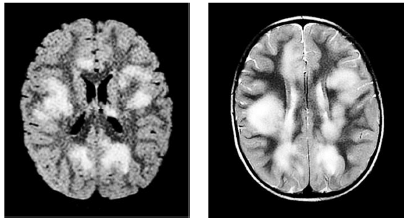

Paciente de 4 anos de idade, com antecedente de quadro gripal há uma semana, evoluiu com alteração do nível de consciência, crises epilépticas focais e hemiparesia à direita. A análise do líquido cefalorraquidiano mostra pleocitose (20 células), com predomínio linfomonocitário e hiperproteinorraquia (80 mg/dL). Os exames de imagem são mostrados a seguir. Foi feita pulsoterapia com corticoide, evoluindo favoravelmente, com recuperação clínica total.

A respeito desse caso clínico hipotético, julgue o seguinte item.

Com base nos exames laboratoriais e de imagem desse paciente, o diagnóstico mais provável é de encefalomielite aguda disseminada (ADEM).